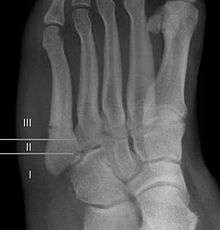

A legitimate concern in any fracture is whether the fracture will heal quickly and without complication. Failure of the fractured ends to unite is called non-union and its frequency varies with the fracture site, some fracture sites being notorious for non-union. An example of such would be a scaphoid (navicular) fracture of the wrist. Such a complication also involves fractures of the proximal end of the fifth metatarsal, such as the Jones fracture. This has been the subject of interest, and initially led to the description of three zones at the proximal end of the fifth metatarsal.

Zones I and II have been associated with relatively guaranteed union and this union has taken place with only limited restriction of activity combined with early immobilization. On the other hand, zone III has been associated with either delayed or non-union and, consequently, it has been generally agreed that fractures in this area should be considered for some form of internal immobilization, such as internal screw fixation. More recently, because of the similar behavior of the original zones I and II, it has been suggested that zones I and II be combined leading to current recommendations for two zones, zone I being associated with uncomplicated union, and zone II being prone to nonunion and therefore considered for internal fixation.

These zones can be identified anatomically and on x-ray adding to the clinical usefulness of this classification.[3] It should be emphasized that surgical intervention is not, by itself, a guarantee of cure and has its own complication rate. Other reviews of the literature have concluded that conservative, non-operative, treatment is an acceptable option for the non-athlete.[4]